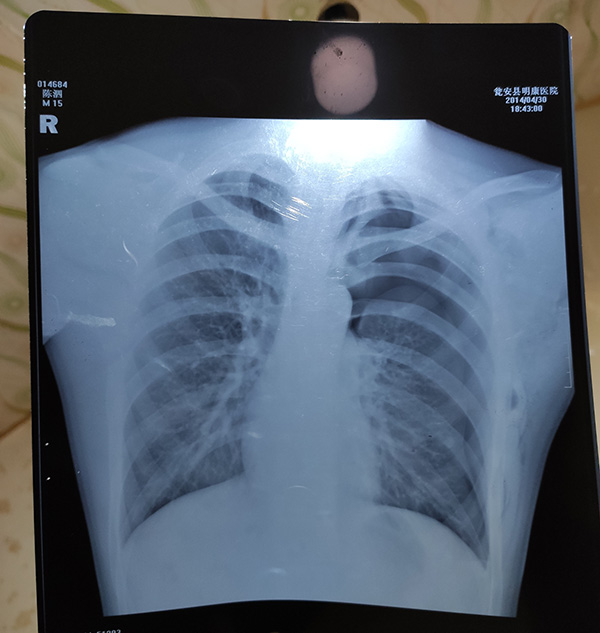

案发当晚 , 陈泗翰的胸片 。

一审后 , 陈泗翰在看守所里写给家人的信 。失控案发当天 , 李荣惠早早把饭做好 , 等孩子们回来 。 一直等到五点多 , 噩耗降临 。赶往瓮安的路上 , 他们接到医院打来的电话 , 说再不做手术 , 你儿子就等不到你们了 , “最多20分钟” 。 李荣惠脑袋一嗡 , 陈善坤也蒙了 。 四姐抢过手机说马上做手术 , 到了再补签字 。赶到时手术已结束 , 人还在昏迷中 , 医生下了病危通知书 。 当晚的胸片报告显示左肺被压缩约75% , 经县公安局法医鉴定为重伤二级 。